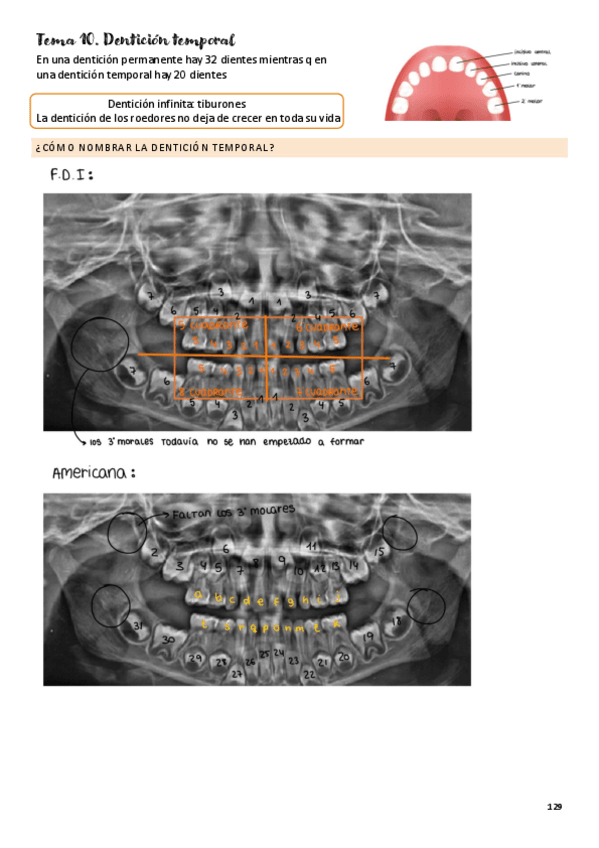

Apuntes - tema-10-denticion-temporal.pdf